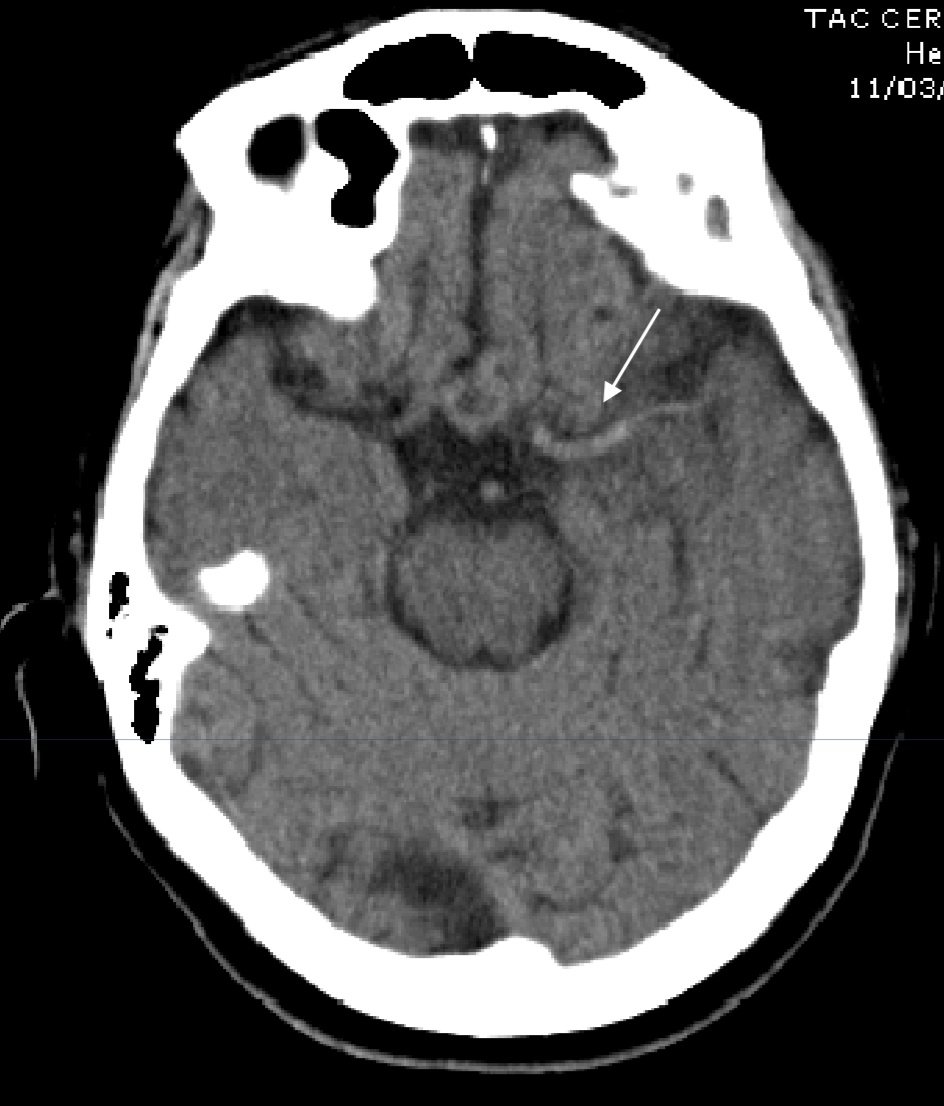

Se Observa El Signo De La Cuerda Dado Por La Hiperdensidad De La Download Scientific Diagram

Multimedia En Medicina 34 Signo De La Cuerda Interconsulta On Line